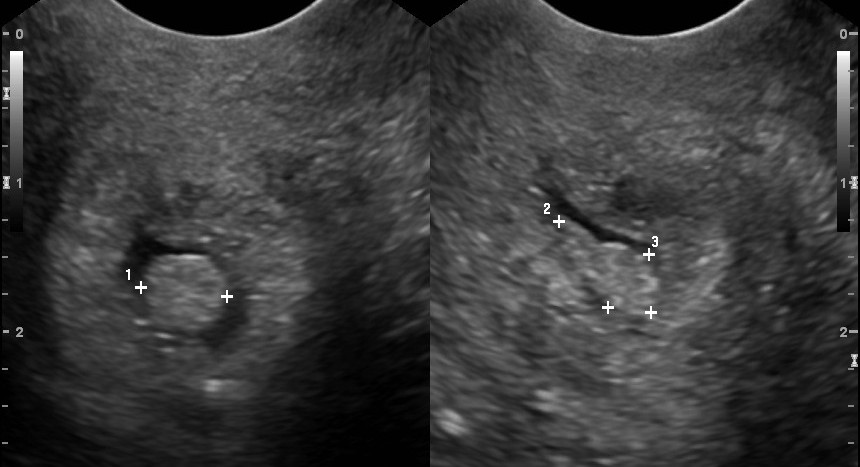

На ранніх етапах хвороба підступна своєю тишею. Жінка може роками не підозрювати про проблему, допоки утворення не буде знайдене випадково під час планового огляду чи кольпоскопії. Також добре видно поліп цервікального каналу на УЗД-фото. По мірі росту утворення починають проявлятися характерні ознаки:

Іноді пацієнтки запитують, чи поліп цервікального каналу видно на УЗД. Так, сучасні апарати дають можливість помітити утворення навіть при невеликих розмірах. Його видно по локальному потовщенню або чіткому включенню в просвіті шийки матки. Воно зазвичай має структуру щільнішу, ніж навколишні тканини, і чітко виділяється на моніторі.